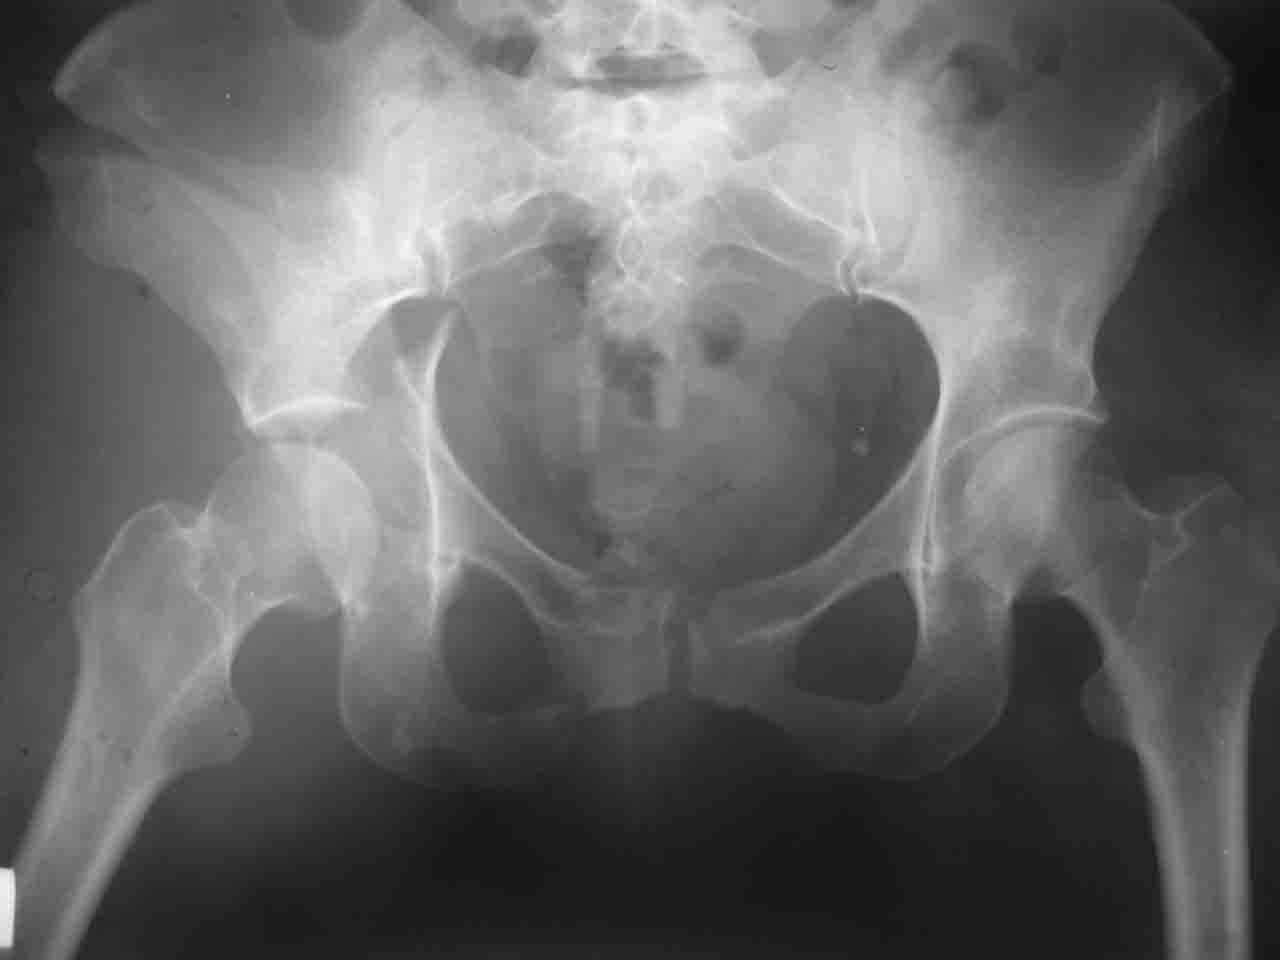

Логика подсказывает, что все-таки лучше иметь анатомически полноценную впадину, хотя ранее упоминалось состояние вторичной конгруэнтности и одно наблюдение у меня есть, когда у больного с полностью нарушенной анатомией впадины и подвывихом головки бедра кзади и кверху боли отсутствовали при относительно достаточном для стиля жизни больного объёме движений. Но это только одно наблюдение и кроме перелома впадины у этогобольного была и тяжелая ЧМТ в анамнезе. Основываясь на формулировке структуры ацетабулюм Э. Летурнеля - как перевернутой буквы Y, впадина для полноценной функции сустава должна иметь сферичность, соответствующую размеру головки бедра и если один из компонентов в дефиците, то функциональные последствия рано или поздно проявятся.

Вопрос доступа к вертлужной впадине при остеосинтезе задача не простая. Конечно, у Летурнеля и Тайла всё давно описано, нам остается только брать на вооружение. Но сами понимаете, что не бывает двух одинаковых ситуаций, поэтому в каждом случае вопрос решается сугубо индивидуально. Наша главная цель - восстановить анатомию с нанесением минимальной дополнительной травмы тазобедреннному суставу, думаю с этим никто не поспорит. Расширенный илиофеморальный доступ уж слишком травматичен (как сказал один коллега "таз лежит отдельно, больной отдельно").Стоит ли делать из пациента анатомический препарат для того чтобы легче ориентироваться. Да и нужно ли собирать всю "мозаику"? Мы применяли при таких операциях своеобразную операционную хитрость - сначала устраняли грубое смещение крыла под гребнем с фиксацией так называемой "плавающей" пластиной (временно фиксированной на двух винтах)- доступ или продлевали боковой, или делали небольшой дополнительный разрез над гребнем. Это позволяло устранить грубое смещение и захождение отломков тела повздошной кости, что значительно облегчало репозицию и остеосинтез впадины над сводом. Основное внимание конечно же уделяли нагружаемому задне-верхнему отделу. Сообщите ваш адрес, пришлю схемы и рентгенограммы.